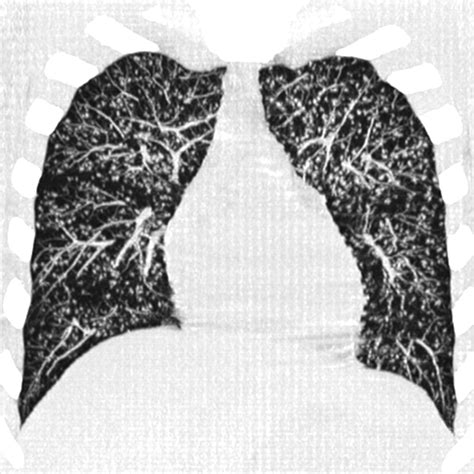

When you receive a radiology report mentioning tree in bud opacities, it can be an unsettling experience. This specific term is used by radiologists to describe a distinct pattern of lung abnormalities seen on high-resolution computed tomography (HRCT) scans. Understanding what this pattern means is crucial, as it acts as a diagnostic clue for healthcare providers to narrow down the underlying cause of your symptoms. Essentially, the term refers to the visual appearance of small, branching opacities in the peripheral airways, resembling a tree with buds at the end of its branches. While this finding is never a diagnosis in itself, it is a significant radiological sign that requires clinical correlation to determine the appropriate course of treatment.

The tree in bud opacities appearance is fundamentally a reflection of airway pathology. On a CT scan, the "tree" component represents dilated, fluid-filled bronchioles (the smallest airways in the lung), while the "buds" represent the accumulation of mucus, pus, or fluid in the acini, which are the functional units of the lung located at the ends of these bronchioles. This pattern typically suggests that something is causing inflammation, infection, or obstruction within the small airways.